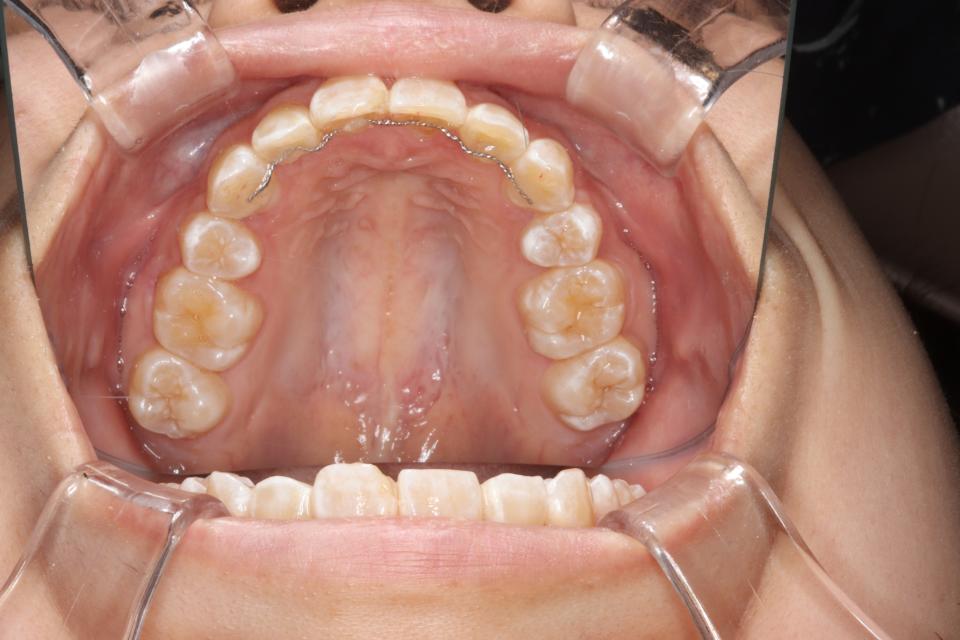

がたがた(叢生)のワイヤー矯正治療例(抜歯あり)

矯正治療前

20代女性の患者さんです。

下の前歯のがたつきを気にして来院されました。

上左右4番抜歯をして、上下の歯にワイヤー(マルチブラケット装置)をつけて治療しました。

きれいに並びきるために歯のやすりがけ(IPR)も行っています。

歯並びを並べる治療は終わり、現在は前歯の裏側にワイヤーをつけ、それと同時に

取り外しのできる装置をはめることで後戻りの防止をして、